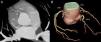

A 74-year-old man, with a history of heavy smoking, presented with unstable angina (Figure 1). Dobutamine stress echocardiography showed ischemia in the right coronary artery territory. Coronary angiography revealed no obstructive epicardial disease in the left dominant circulation (Figure 2A); the right coronary artery (RCA) was a small caliber and tortuous vessel, with only minor atheroma. However, an abnormal vessel arising from the proximal RCA was noted (Figure 2B and C), confirmed as a fistulous connection to the left atrium by multislice computed tomography, which also excluded other vascular anomalies (Figure 3). This was deemed to be causing a coronary steal phenomenon. Exercise myocardial perfusion imaging under anti-ischemic therapy excluded residual ischemia and the patient was successfully conservatively managed (Figure 4).

(A): coronary angiography depicting no obstructive epicardial disease in the left dominant coronary circulation. (B and C): the right coronary artery was a small caliber vessel, with significant tortuosity in its proximal segment, but with no obstructive disease. An abnormal vessel was noted (arrows) arising from its proximal course and heading left, toward a posterior-superiorly located structure. LAD: left anterior descending artery; LCx: left circumflex artery; RCA: right coronary artery.